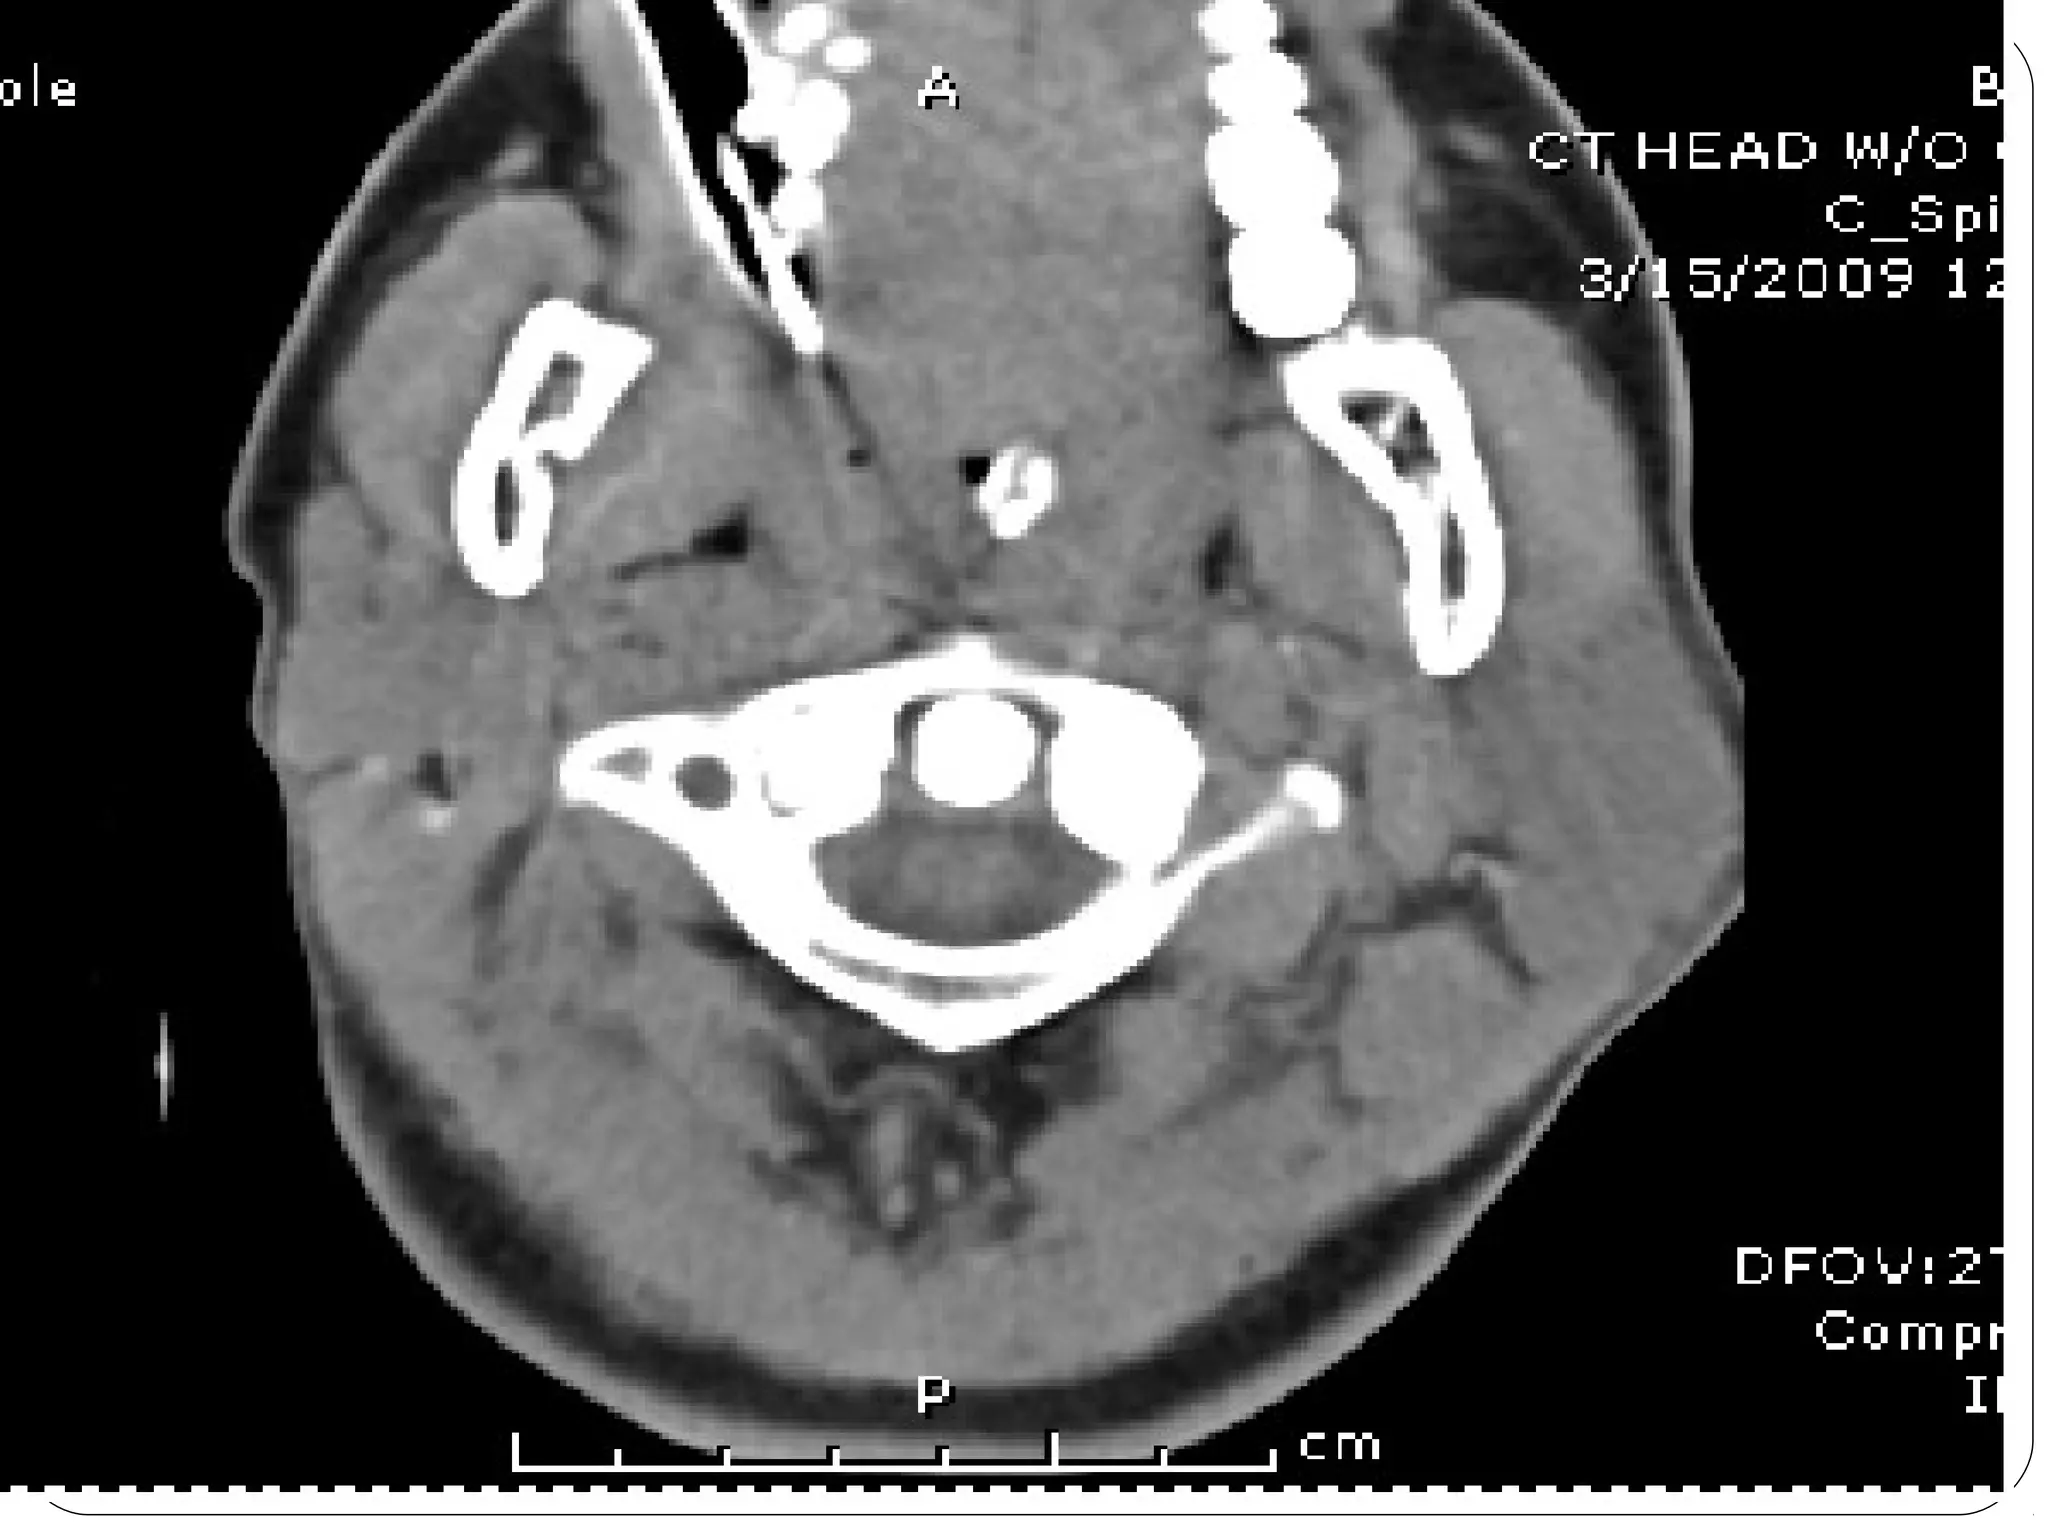

Computed Tomography (CT)

1. Also called CAT scanning or “CT”

2. X-Ray beam moves 360 around the patient

3. Consecutive x-ray “slices” around the patient

4. Computer can recreate 3D image of the body or

Image “slices” reconstructed by computation

5. Best for evaluating bone and soft tissue tumors,

fractures, intra-articular abnormalities, and

bone mineral analysis

Computed Tomography

6. The image formed is related to the subjects

density

7. Image display on computer or multiple films

8. New technology is multislice helical scanner

CT (by Picker)

LV

VERTEBRAL

BODY

SPINAL

CANAL

TRANSVERSE

PROCESS

RIB

LUNG

RA

LA

RV

AORTA